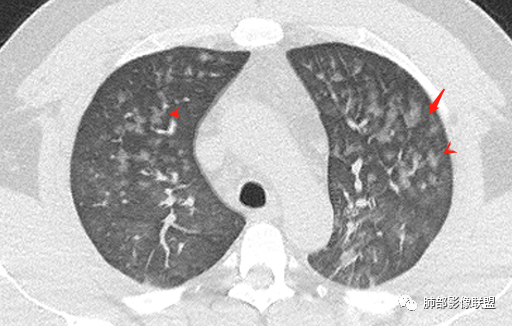

双肺多发弥漫性磨玻璃结节影,大小不一,形态不规则,部分融合,支气管未见明显扩张,部分血管束略增粗,叶裂胸膜增厚,临床有痛风,左足痛6天,考虑:1:痛风结节(一般实性结节,很少磨玻璃结节影)2:血管炎?3:病毒性肺炎(水痘-疱疹肺炎?)

双肺多发腺泡结节及磨玻璃,小叶间隔增厚(大网格状),腺泡结节内及磨玻璃内可见细网格影(小叶内间隔增厚),影像表现符合肺泡出血改变,血肌酐升高,考虑肺肾综合征。鉴别肺水肿。

年轻男性,痛风史,高血压史,肌酐高,左足痛6天入院。胸CT:双肺多发弥漫性磨玻璃结节影,大小不一,部分融合,上中下肺都有,中内带多,胸膜下少。部分血管束略增粗,小叶内间隔、小叶间隔增厚,下肺明显,左室大。叶裂胸膜增厚。临床有痛风,左足痛6天,考虑:心衰、间质性肺水肿?弥漫性肺泡出血?鉴别:MPA,肺肾综合征,痛风结节等。

双肺多发腺泡结节及斑片状磨玻璃影,边缘不清,后者内见细网格状改变,小叶间隔增厚,呼吸系统症状不明显,考虑肺水肿,过敏性肺泡炎代排

双肺多发腺泡结节及磨玻璃网格影,部分融合,小叶间隔增厚,双肺中轴间质增厚不明显,疾病谱:病毒性肺炎,肺泡出血,水肿,过敏性,肺泡蛋白沉着症,PCP。结合病史,没有咳血,肺泡出血,不考虑,过敏没有任何临床症状,而且无上肺分布优势,也排除。病毒性肺炎也无临床支持,排除。PAP影像不典型,暂排除。有肾功能异常,所以考虑1肾源性肺水肿。2,有无激素使用史或HIV,PCP待排。

多发GGO结节,边界清,以全小叶、小叶中心为主:

GGO背景

小叶间隔增厚,无明显重力趋势

中轴间质增厚,小叶间隔增厚,小叶内间质增厚,部分重力作用,双侧对称,胸水,按理淋巴道回流受阻有

问题是腺泡结节如何解释?

一般吸入性病变,肺泡腔充填性病变